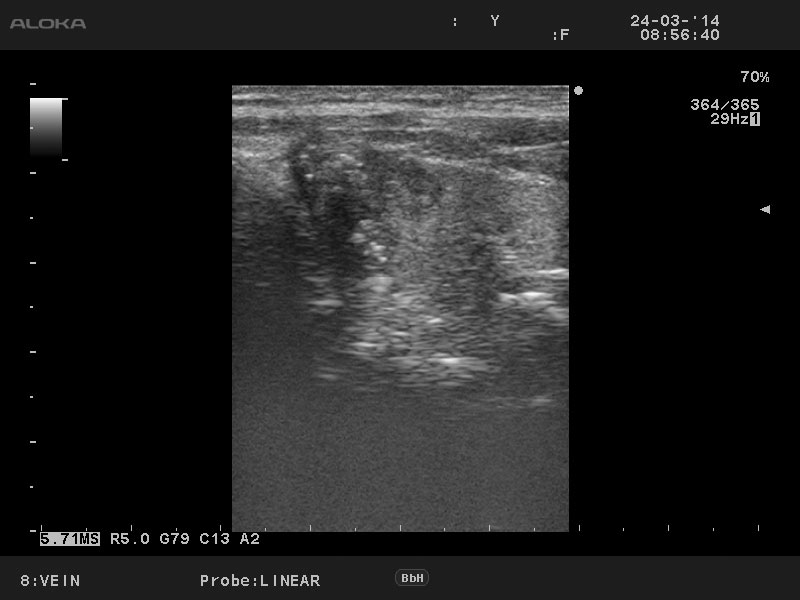

Мужчина 50 лет, жалоб нет.

aml_20140324_VEIN_0014.jpg

Лимфоузел

Диагноз доказан цитологически.